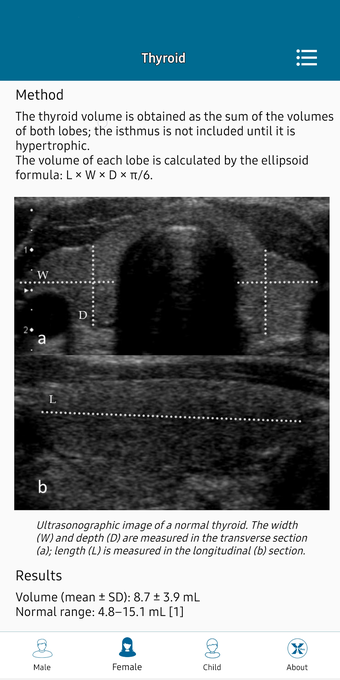

This helpful app is intended for all those who practice medical imaging and for the radiologists who use the application in their work. It is an atlas of the main measurements in radiology and their normal values, divided into six subspecialties: osteoarticular, cervical region, thorax, cardiovascular, abdomen, and pelvis.

The lessons are organized in a way that allows for easy and fast access to the information. In addition, the application has a section with a summary of the main points of the sub-specialties, which can help the user quickly grasp the meaning of the measurements and the importance of each of them.